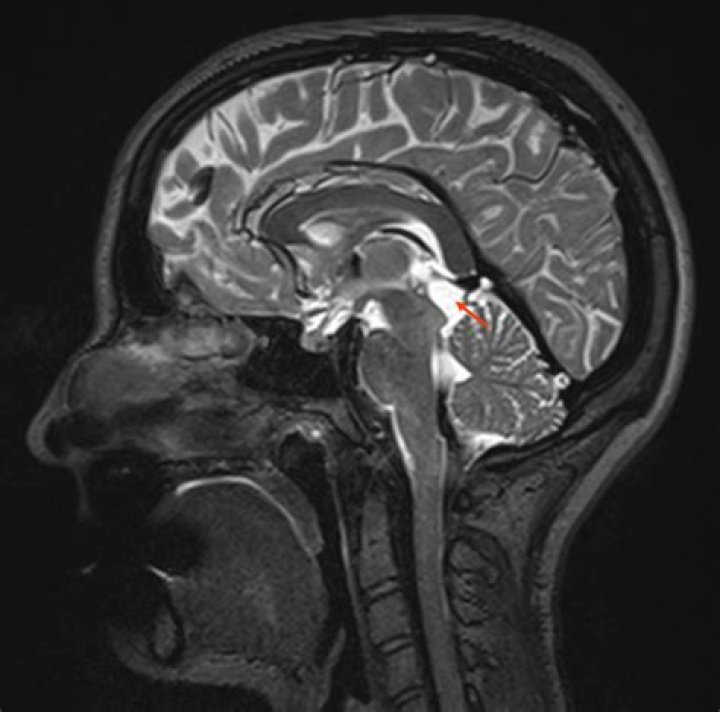

Where is a pineal cyst?

Scarlett Howard Pineal cysts are fluid-filled spaces within the pineal gland. The pineal gland sits nearly in the center of your brain, and is responsible for hormones related to sleep-wake cycle. Pineal cysts are common, occurring in about 1-5% of the population. These cysts are benign, which means not malignant or cancerous.

While small benign cysts of the pineal gland are a common incidental autopsy finding in the adolescent and adult years, lesions larger than 0.5 cm in diameter are rare. Cysts 2 cm or larger may cause neurologic symptoms and signs from aqueductal obstruction and tectal compression.

It has been previously reported that pineocytomas can mimic typical pineal cysts in imaging appearance1–13; it has been our experience, however, that when fully and completely imaged—which necessitates using postcontrast MR imaging—most of these tumors bear little resemblance to typical pineal cysts.